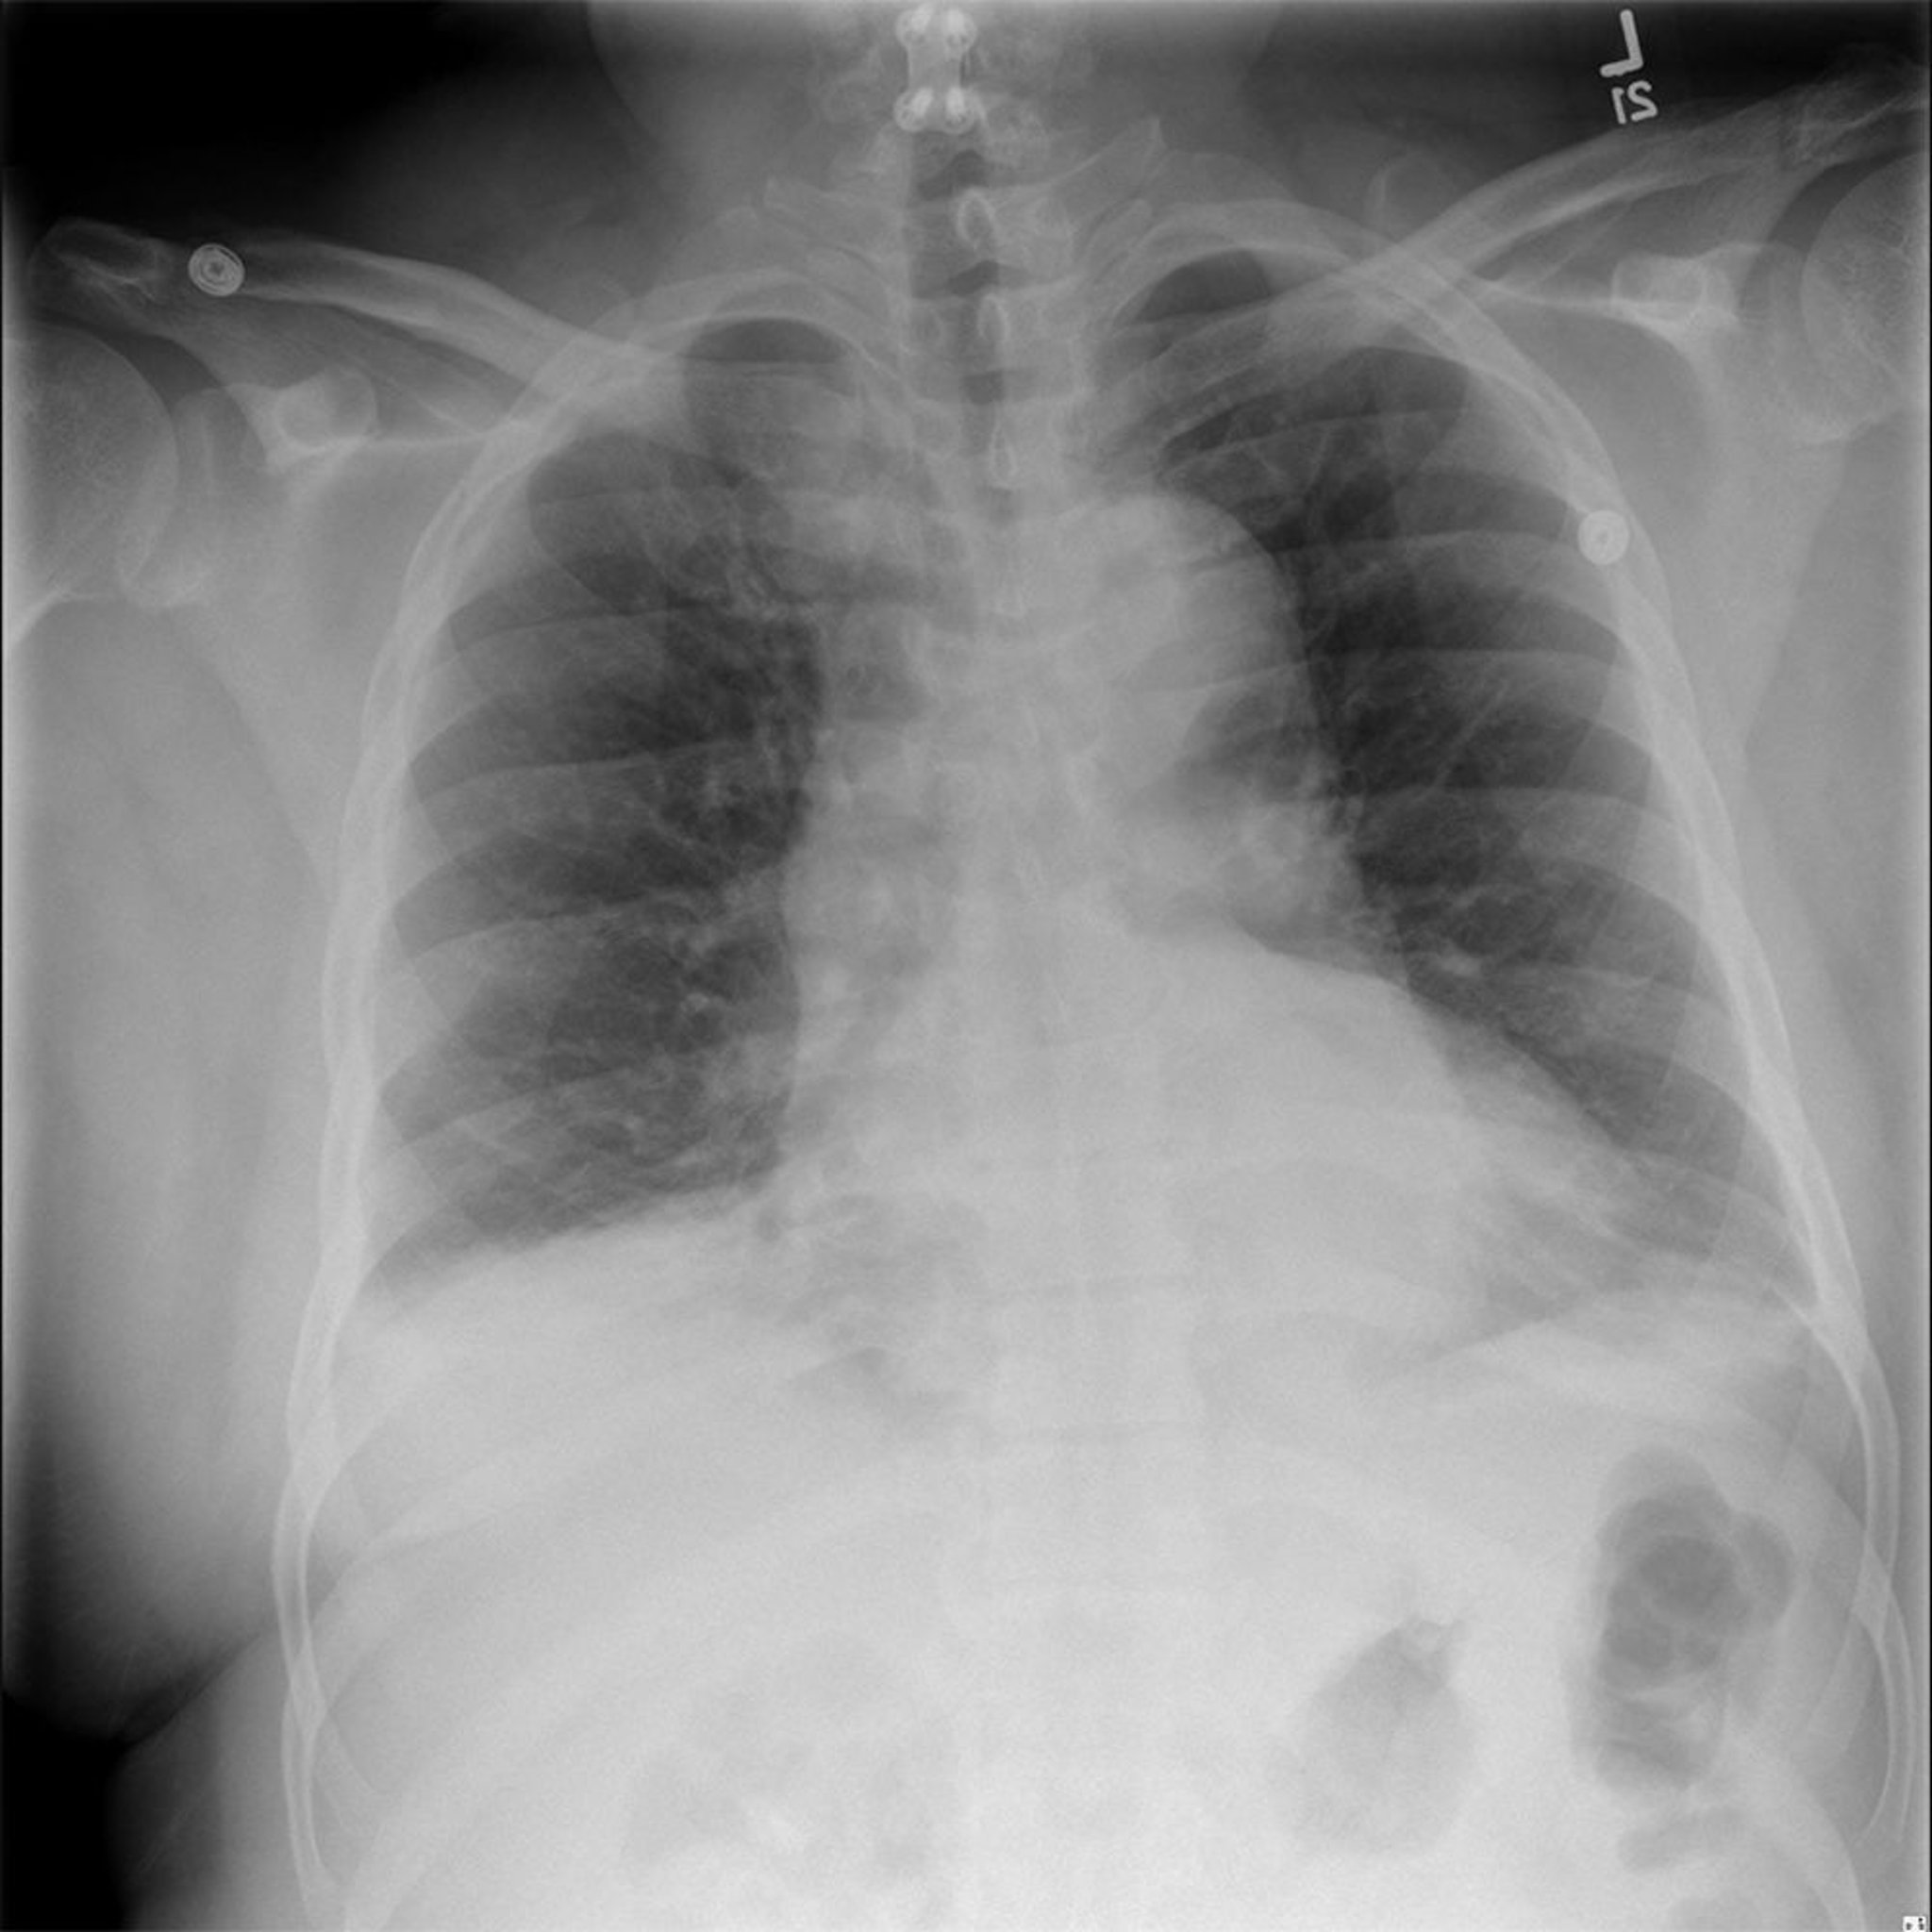

Mediastino dilatado

Esta radiografía muestra el mediastino dilatado de un paciente con aneurisma de aorta torácica diagnosticado.